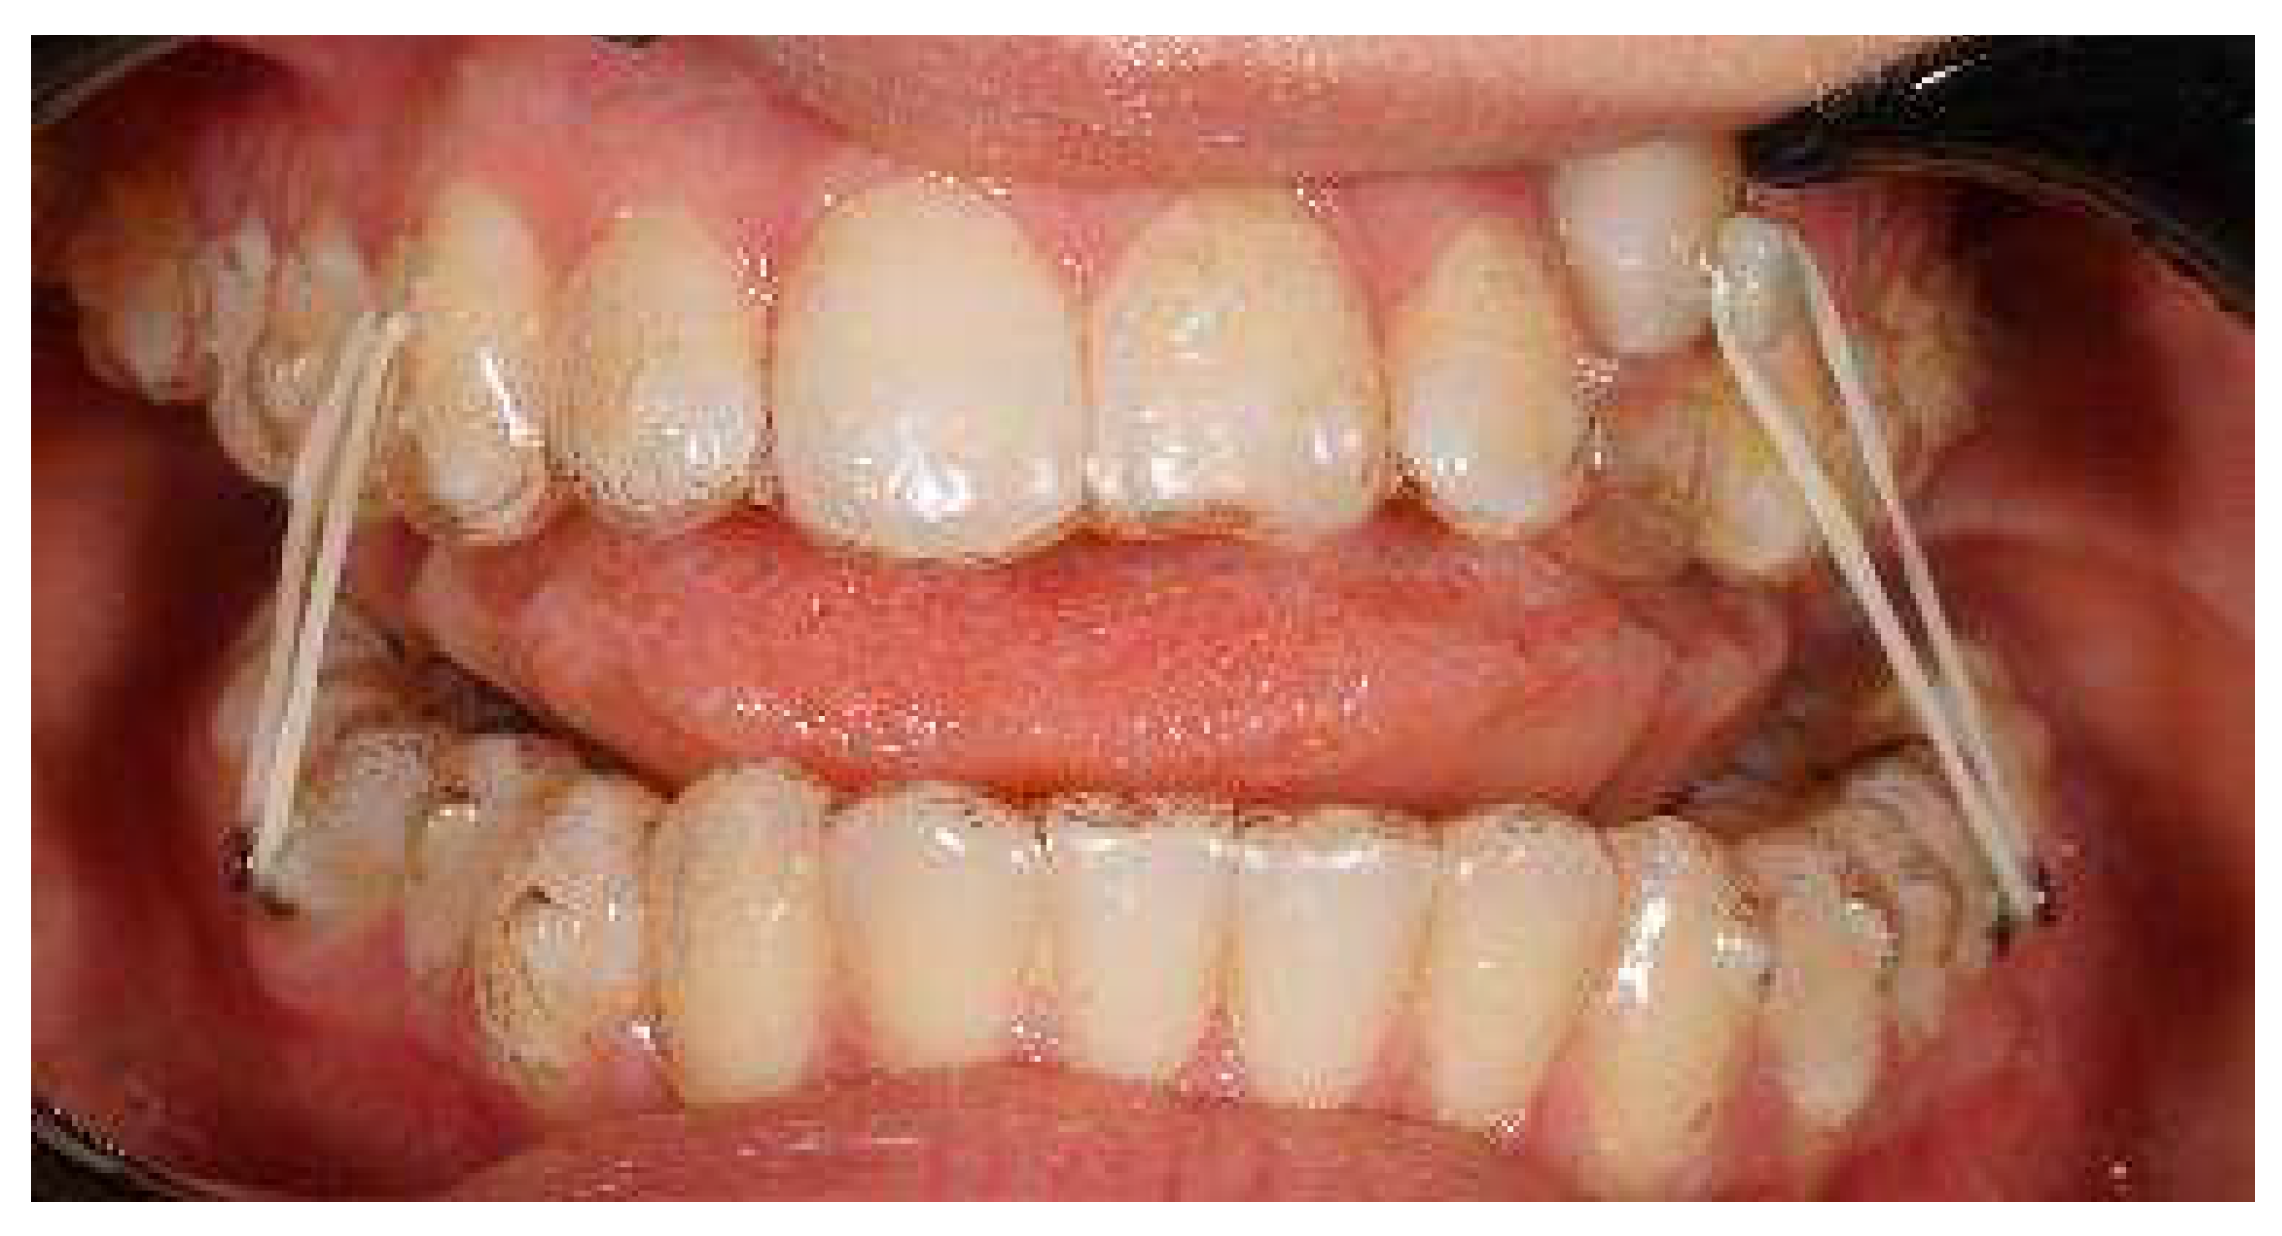

An 18-year-old female patient was referred, complaining of unpleasant smile. She presented good general health and no systemic or congenital diseases. From a frontal view, the patient presented a well-proportioned three-thirds of her face and no evidence of asymmetry. From the lateral view, the profile appeared convex with well-represented nasolabial angle, labiomental sulcus, and lip competence. Intraorally, the patient showed a Class II malocclusion with the molar Class I relationship, edge to edge canine relationship on both sides, increased overjet, overbite, and the retention of the 63. Panoramic, lateral headfilm, and dental cast records were taken (Figure 11).

Figure 11.

An 18-year-old female with dentoskeletal Class II with impacted upper left canine before treatment.